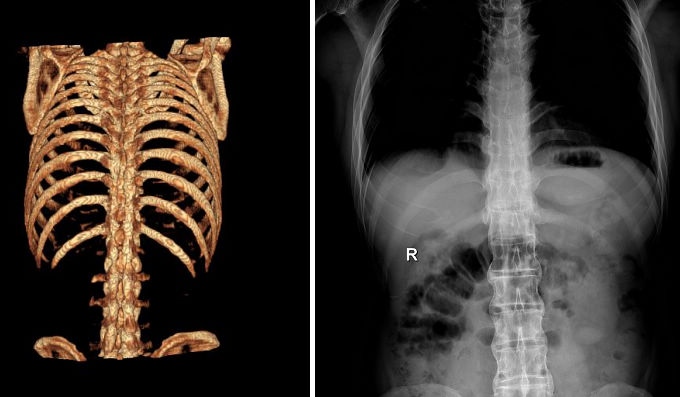

X线检查对AS的诊断有极为重要的意义,约98%~100%病例早期即有骶髂关节的X线改变,是本病诊断的重要依据。

早期X线表现为骶髂关节炎,病变一般在骶髂关节的中下部开始,为两侧性。开始多侵犯髂骨侧,进而侵犯骶骨侧。可见斑点状或块状骨侧明显。继而可侵犯整个关节,边缘呈锯齿状,软骨下有骨硬化,骨质增生,关节间隙变窄。最后关节间隙消失,发生骨性强直。骶髂关节炎X线下易用按钮约诊断标准分类5级:0级为正常骶髂关节,Ⅰ级为可疑骶髂关节两侧炎;Ⅱ级为骶髂关节边缘模糊,略有硬化和微小侵蚀病变,关节腔轻度变窄;Ⅲ级为骶髂关节两侧硬化,关节边缘模糊不清,有侵蚀病变伴关节腔消失;Ⅳ级为关节完全融合或强直伴或不伴残存的硬化。

脊柱病变的X线表现,早期为普遍性骨质疏松,椎小关节及椎体骨小梁模糊(脱钙),由于椎间盘纤维环附带部椎骨上角和下的破坏性侵蚀,椎体呈“方形椎”,腰椎的正常前弧度消失而变直,可引起一个或多个椎体压缩性骨折。病变发展至胸椎和颈椎椎间小关节,间盘间隙发生钙化,纤维环和前纵行韧带钙化、骨化、韧带骨赘形成,使相邻椎体连合,形成椎体间骨桥,呈最有特征的“竹节样脊柱”。

原发性AS和继发于炎性肠病、Reiter综合征、牛皮癣关节炎等伴发的脊柱炎,X线表现类似,但后者为非对称性强直。在韧带、肌腱、滑囊附着处可出现骨为和骨膜炎,最多见于跟骨、坐骨结节、髂骨嵴等。其它周围关节亦可发生类似的X线变化。

早期X线检阴性时,可行放射线核素扫描,计算机断层和核磁共振检查,以发现早期对称性骶髂关节病变。但必须指出,一般简便的后前位X线片足可诊断本病。